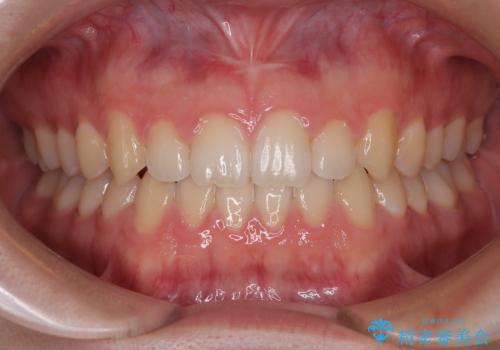

[ セラミック治療 ] 前歯の見た目を改善したい

担当医 大元洋佑